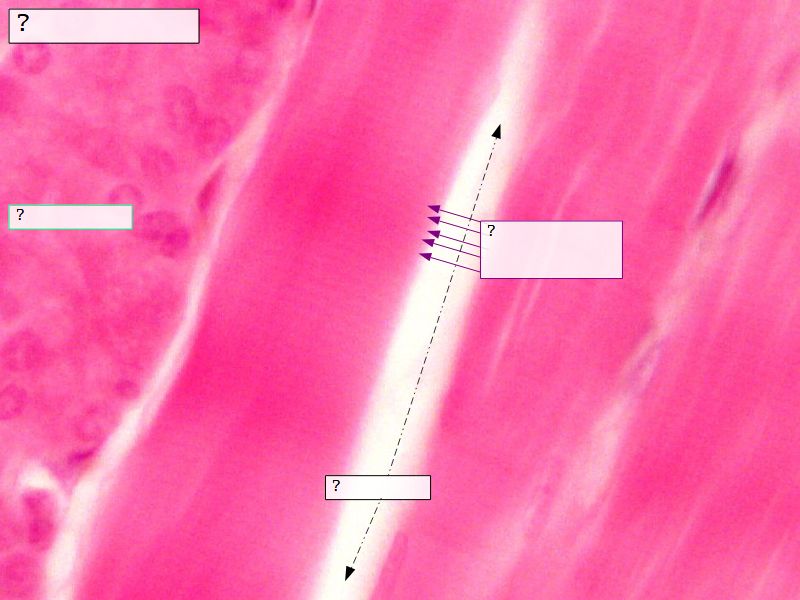

Fill in all the missing labels, and assess as you move through the slides. Answers on the down slide. It is important to do this using pen and paper, and not just glance through the images.